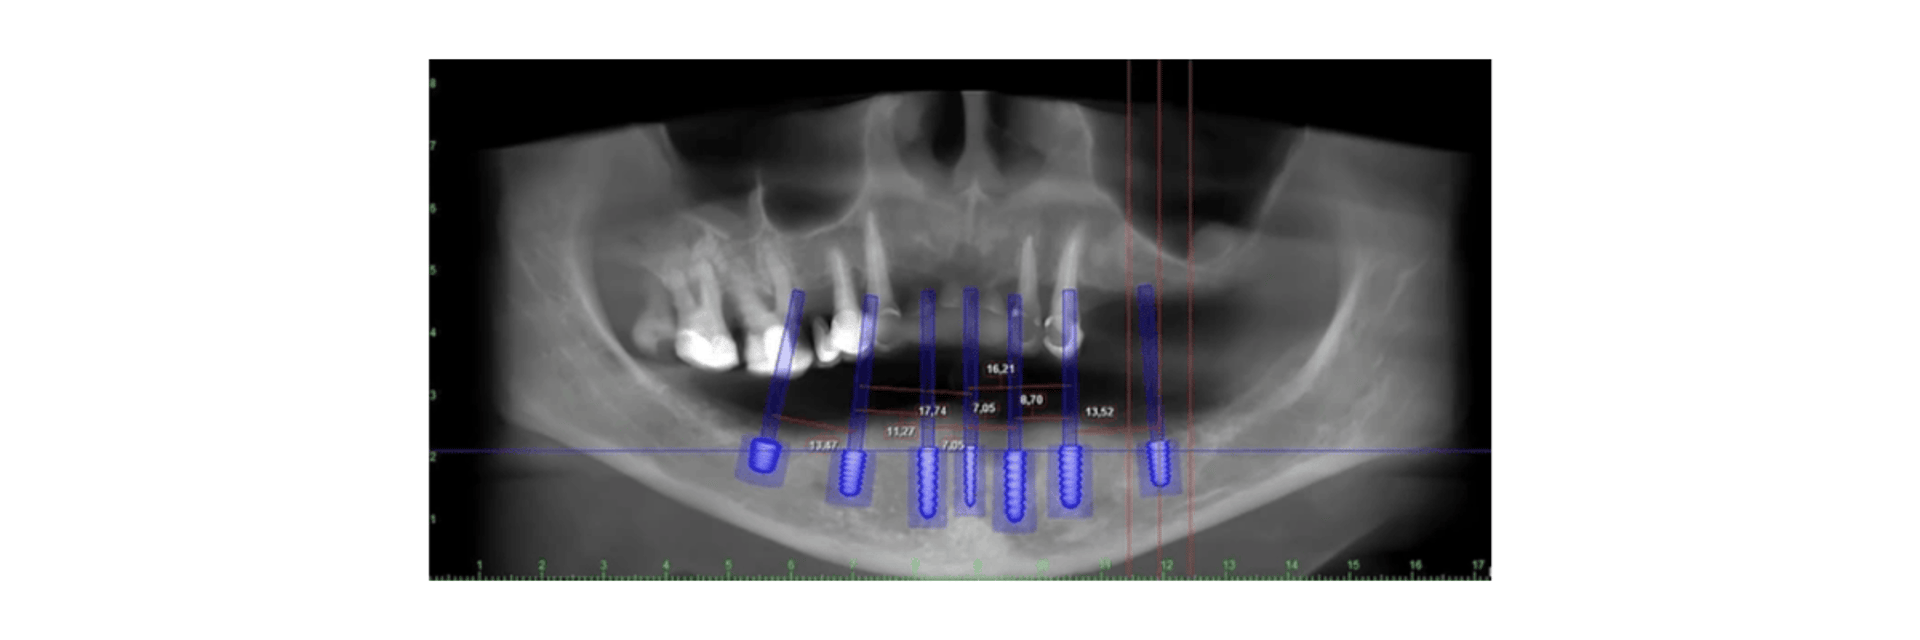

Es la integración tecnológica que automatiza y conecta las etapas clínicas (diagnóstico, planificación y tratamiento) mediante herramientas digitales como escáneres intraorales, software CAD/CAM e impresión 3D. Sustituye los métodos analógicos tradicionales (moldes de silicona) por datos 3D, mejorando la precisión, rapidez y experiencia del paciente.

Adquisición/Digitalización: Se inicia capturando imágenes 3D directamente de la boca con escáneres intraorales o mediante radiología 3D (tomografía).

Planificación (Software CAD): Se utiliza software de diseño asistido por computadora (como ExoCAD o 3Shape) para diseñar prótesis, férulas o planificar implantes.